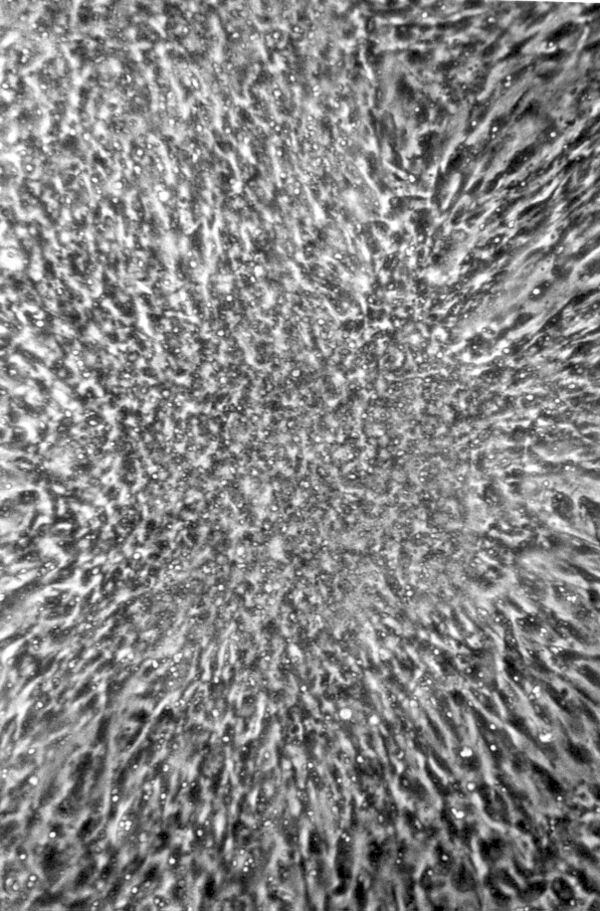

Процесс малигнизации в клеточных культурах — in vitro